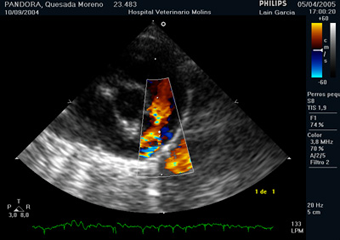

Figura 1. Ecocardiografía en modo Doppler color. Se observa un flujo turbulento que se origina cerca de la bifurcación de la arteria pulmonar y se dirige hacia la válvula pulmonar.

Al realizar el estudio del tronco pulmonar con Doppler color se observa un flujo de aliasing que se origina cerca de la bifurcación y que choca contra la válvula pulmonar. En el Doppler espectral aparece un flujo continuo. El gradiente de presión del flujo que discurre a través del CAP debe ser aproximadamente de 100 mmHg, lo que equivale a un pico de velocidad del jet de unos 5 m/s. Si ya se ha instaurado hipertensión pulmonar, este gradiente puede ser menor. Es habitual detectar un incremento en la velocidad del flujo aórtico por el aumento en la precarga, por lo que debemos descartar un CAP en los casos en que se detecte aumento de velocidad en el tracto de salida del ventrículo izquierdo en ausencia de estenosis aórtica.